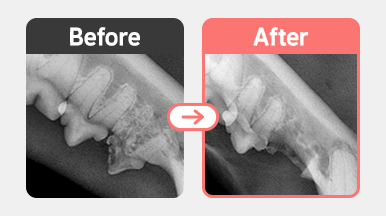

방사선 검사 결과, FORL Type 3 병변이 두 부위에서 확인되었습니다.

① 부위 1 – 치근이 남아 있는 상태 (Type 3)

치관과 치근 모두 병변이 진행된 상태로,

치근을 포함하여 완전 발치 진행

② 부위 2 – 치근이 이미 흡수된 상태 (Type 3, Type 2 양상 혼합)

치근이 X-ray상 거의 보이지 않아 Crown Amputation 시행